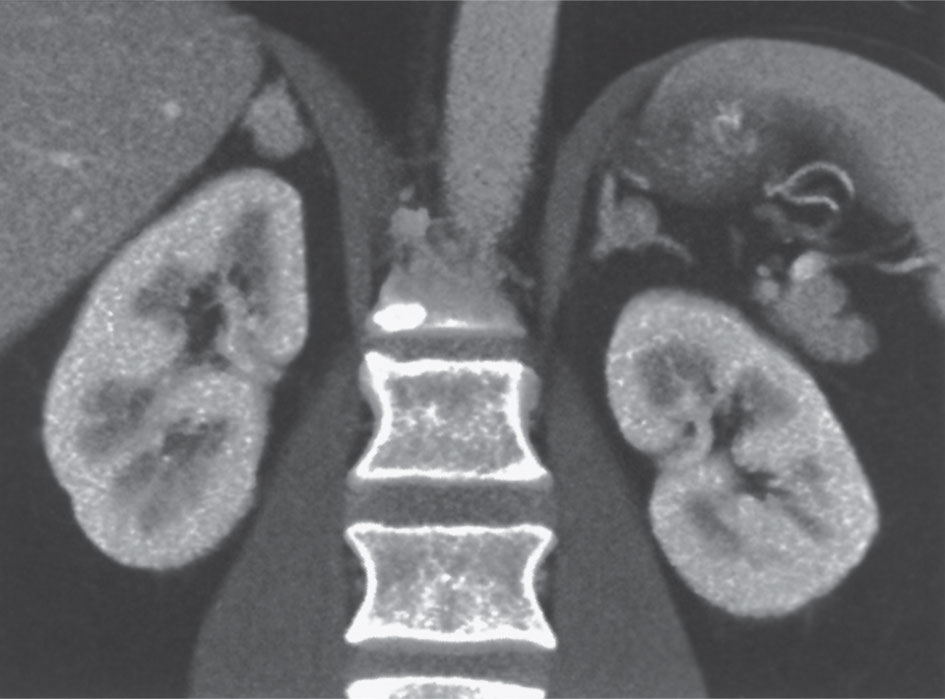

6- تقييم أورام الكظر قبل الحقن وبعده؛ إذ من المعروف أن الأورام الكظرية السليمة تكون عادة منخفضة الكثافة قبل الحقن مقارنة بالأورام الخبيثة والنقائل، ويزول توهجها بعد الحقن على نحو أسرع مقارنة بالأورام الخبيثة (الشكل 16).

![]()  | ![]()  | |

الشكل (16) تصوير مقطعي محوسب للبطن مع الحقن مع إجراء إعادة تشكيل إكليلية تظهر كتلة صغيرة في كل غدة كظرية، وكانت نسبة زوال التوهج بعد الحقن (washout) أكثر من 50% مما يتماشى مع ورم غدي كظري سليم.  | الشكل (15) تصوير مقطعي محوسب للبطن بعد الحقن مع إجراء إعادة تشكيل إكليلية تظهر كتلة ورم خلايا انتقالية في الثلث السفلي من الحالب الأيسر مع استسقاء الحالب وجهاز الكلية اليسرى المفرغ.  |